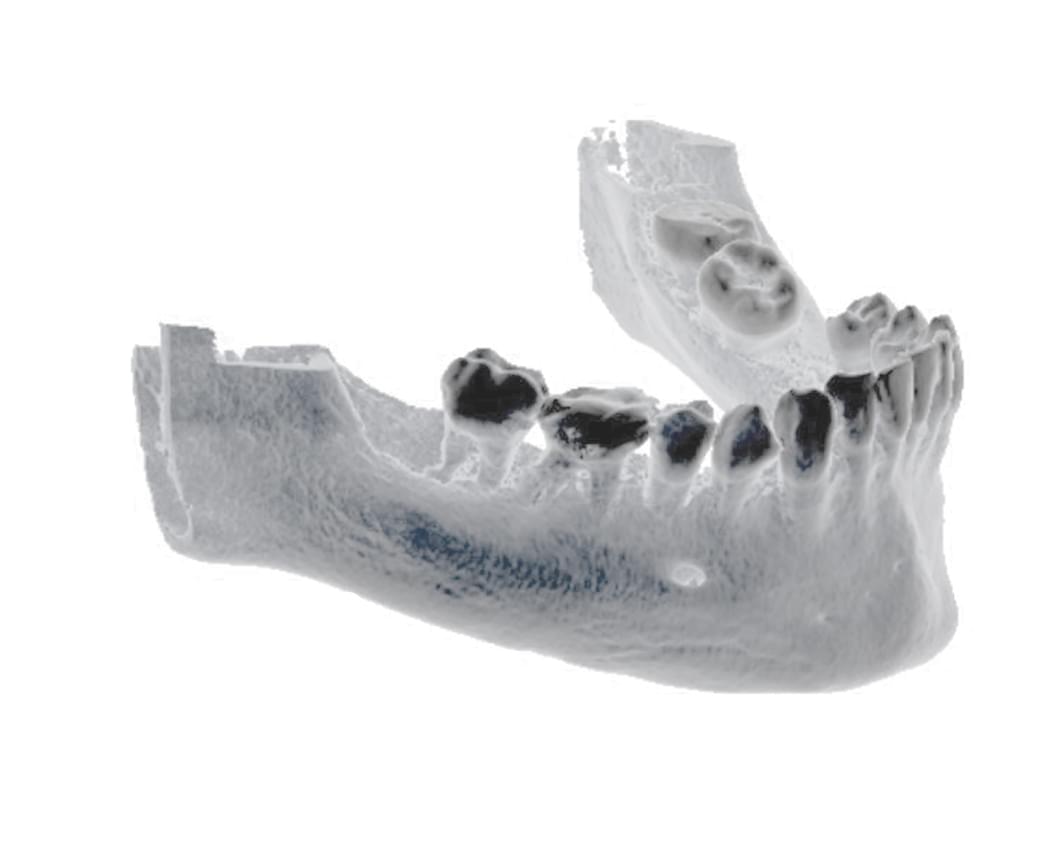

Výpočetní tomografie

(3d čelisťové snímky a snímky ústní dutiny)

CBCT Maxilofaciální diagnostika